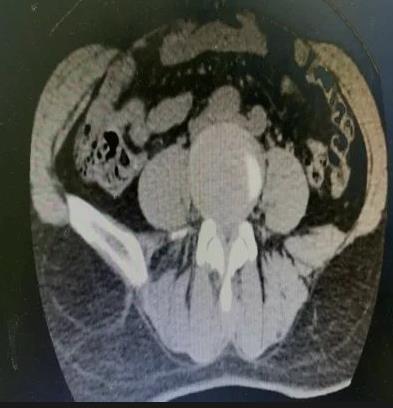

60岁的王某,女性,有3年“腰椎间盘突出伴椎管狭窄”病史。最近,她的腰痛加重,感觉到疼痛向双侧臀部放射,伴有双下肢沉重感。只能走大约300米就需要停下来休息,给她的日常生活带来很大困扰。王某来到市中心医院就诊,与骨科一病区医师详细交流,经仔细检查,发现患者病情比较严重,保守治疗效果不佳,而且狭窄部位比较深,采用普通的单轴椎间孔镜手术可能效果不好。经过骨一科医疗团队共同讨论,决定采用创伤小、恢复快、椎管减压更彻底的微创方案-UBE技术进行治疗。

做好充分准备后,程福宏主任、雷广宇副主任、张波副主任医师和张楠副主任医师等人共同合作,术中采用两个约1cm的切口,通过通道进行操作,对狭窄部位进行减压(ULBD),并摘除了突出的髓核。术后,患者明显感觉到双下肢松弛,可以自如行走,第二天手术后满意出院。